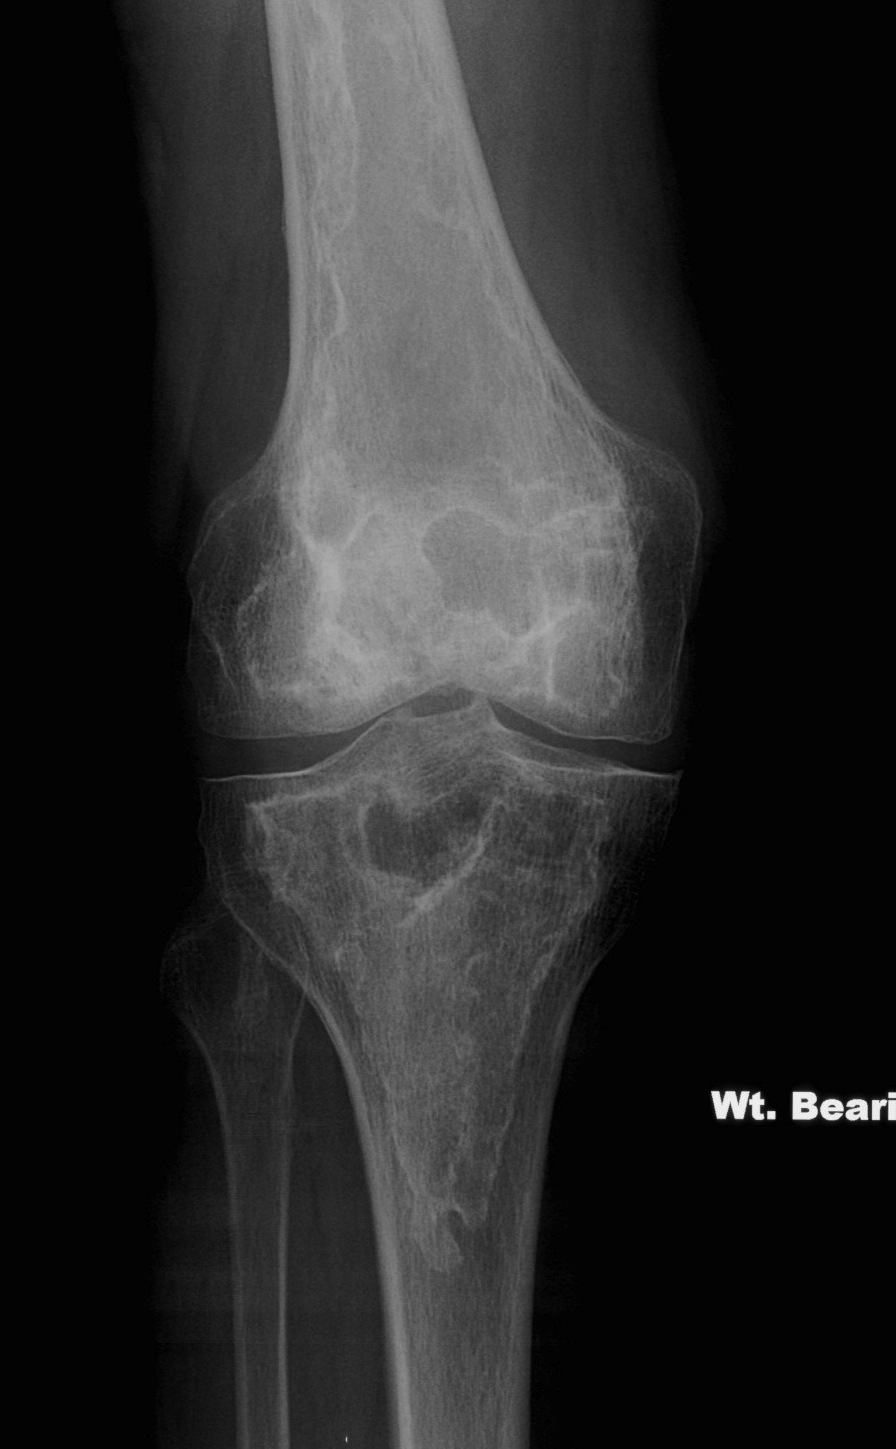

Bone infarct

DDx

Chondroblastoma / Chondrosarcoma

- if in metaphyseal region